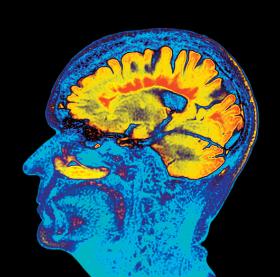

Barwne obrazowanie metodą rezonansu magnetycznego mózgu ze stwardnieniem rozsianym.dr P, Marazzi/Science Photo Library/East News Barwne obrazowanie metodą rezonansu magnetycznego mózgu ze stwardnieniem rozsianym.